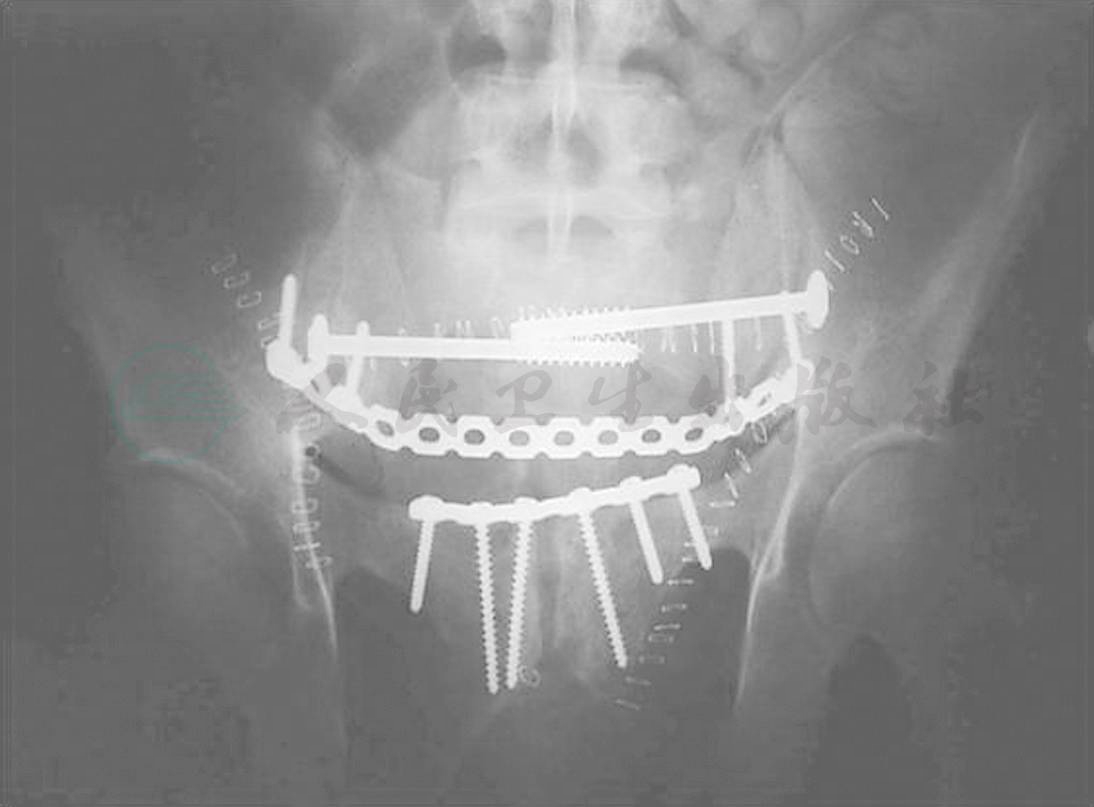

如果患者损伤过重或骨折复位困难,无法行微创治疗,则可行后方减压固定手术。从生物力学角度来看,最稳定的固定是使用下腰椎椎弓根钉和髂骨钉棒系统外加横联的髂腰固定技术(图6及病例2),可以用于神经减压后的固定也可对移位的骶椎椎体进行复位。为了使复位的骨折更加稳定,骶髂螺钉也可作为该技术的补充。由于髂腰固定的巨大稳定性,大部分患者术后可不带支具负重下地活动。

病例2(图9至图15):李某某,男24岁,重物砸伤致骶椎骨折,右下疼痛,肢麻木无力40天。诊断为Roy-Camille 4型骨折,骶神经麻痹,采用椎板切除后路减压及髂腰内固定术。

图14 病例2,术后出口位、正位及侧位X线片